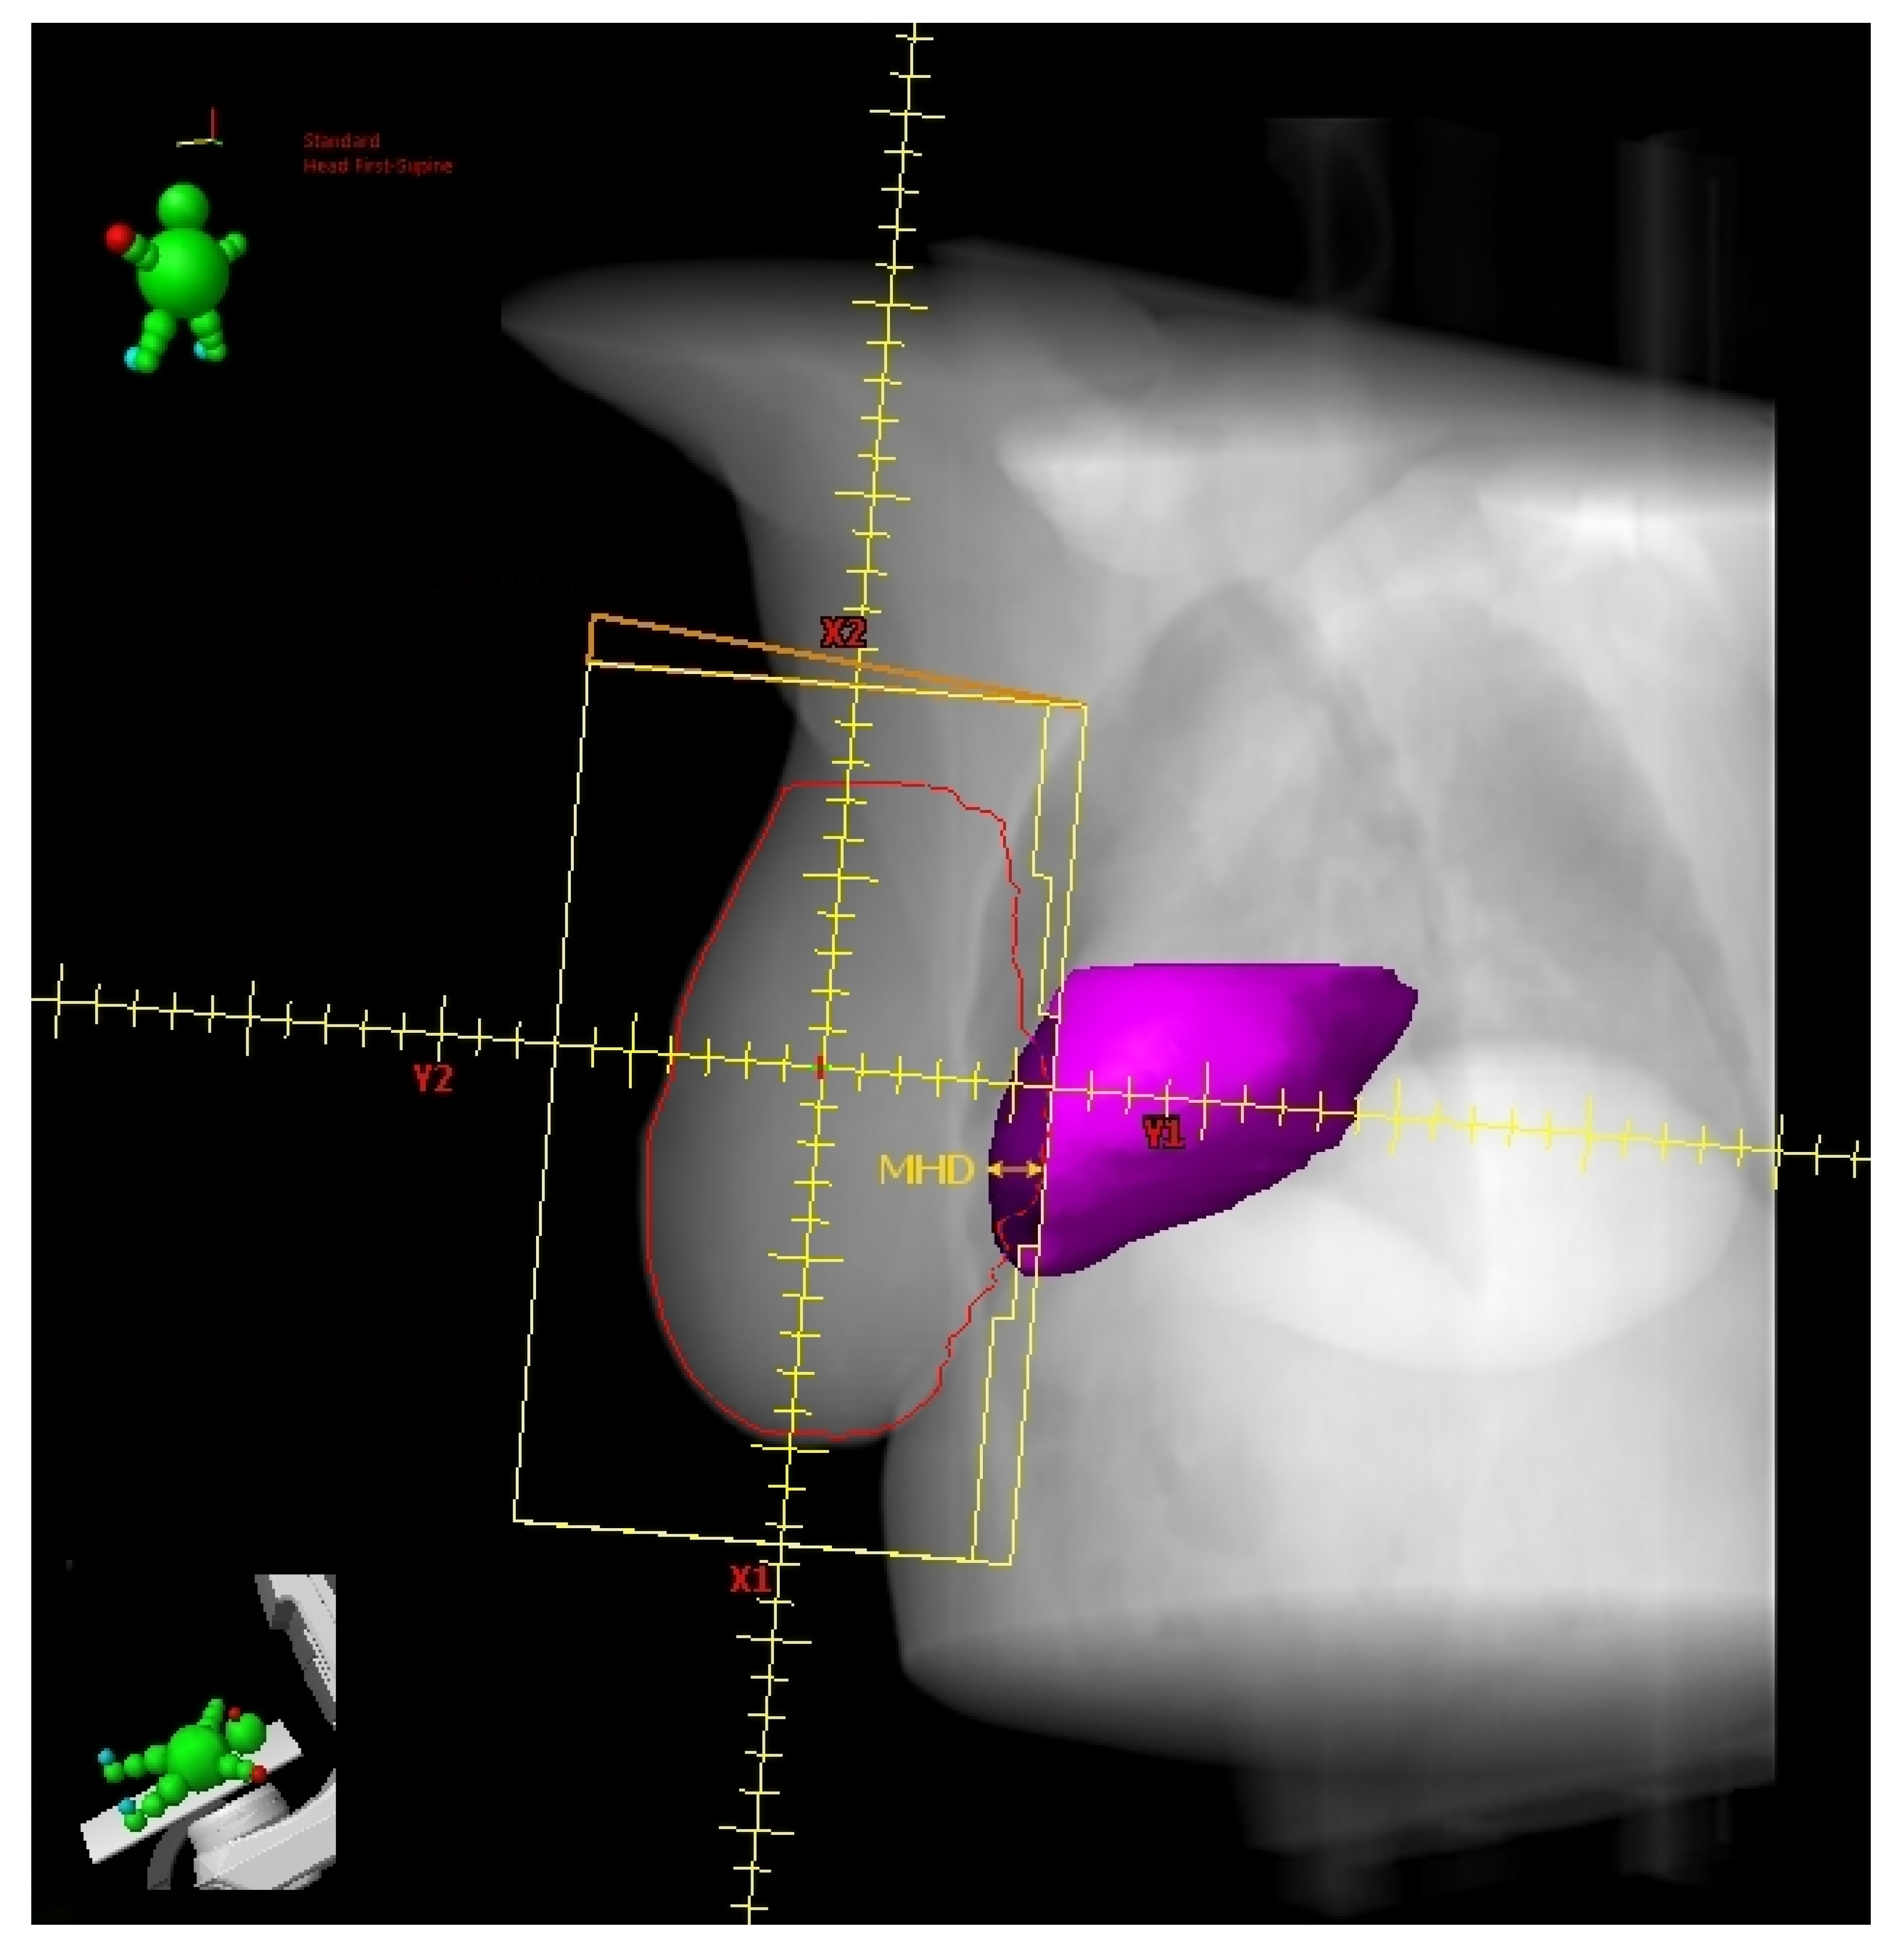

2.5. Maximum Heart Depth and Tumor Bed Site